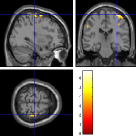

Once the reduced FOV images are available, the proposed pMRI 4D-UWR-SENSE algorithm and its early UWR-SENSE version have been utilized in a final step to reconstruct the full FOV EPI images and compared to the mSENSE Siemens solution. For the wavelet-based regularization, dyadic Symmlet orthonormal wavelet bases [48] associated with filters of length 8 have been used over resolution levels. The reconstructed EPI images then enter in our fMRI study in order to measure the impact of the reconstruction method choice on brain activity detection. Note also that the proposed reconstruction algorithm requires the estimation of the coil sensitivity maps (matrix in Eq. (2)). As proposed in [4], the latter were estimated by dividing the coil-specific images by the module of the Sum Of Squares (SOS) images, which are computed from the specific acquisition of the -space centre (24 lines) before the scans. The same sensitivity map estimation is then used for all the compared methods. Fig. 5 compares the two pMRI reconstruction algorithms to illustrate on axial, coronal and sagittal EPI slices how the mSENSE reconstruction artifacts have been removed using the 4D-UWR-SENSE approach. Reconstructed mSENSE images actually present large artifacts located both at the centre and boundaries of the brain in sensory and cognitive regions (temporal lobes, frontal and motor cortices, …). This results in SNR loss and thus may have a dramatic impact for activation detection in these brain regions. Note that these conclusions are reproducible across subjects although the artifacts may appear on different slices (see red circles in Fig. 5). One can also notice that some residual artifacts still exist in the reconstructed images with our pipeline especially for . Such strong artifacts are only attenuated and not fully removed because of the high level of information loss at .

| mSENSE | 4D-UWR-SENSE | ||

| Axial |  |

|

|

| Coronal | |||

| Sagittal | |||

| Axial |  |

|

|

| Coronal | |||

| Sagittal |